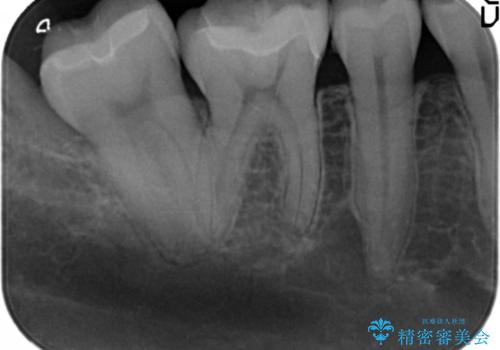

- 笑った時に見える銀歯を白くしたいと希望され来院されました。

現在入っている銀歯を丁寧に除去し、適合の良い精密なセラミックインレーによる修復を行います。

下顎の銀歯はよく見えるのでセラミックに置き替えると見た目の改善が顕著です。